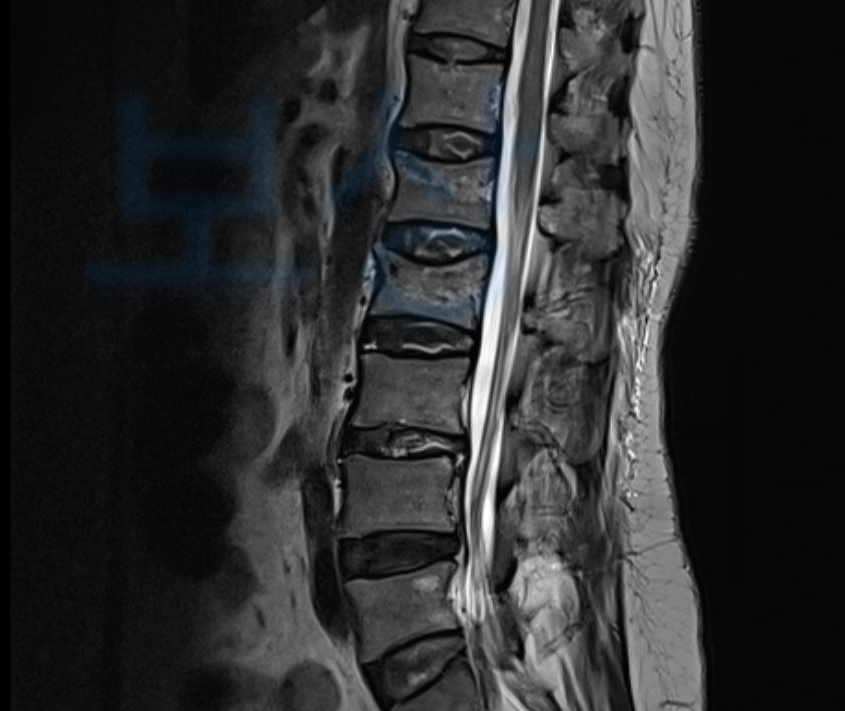

초기 내원한 병원에서 응급처치만 받고 더 큰 병원으로 전원한 의뢰인은 정확한 진단과 치료를 위해 정밀검사를 받게 되셨는데요, 그 결과,

Compression of L1, L2 body

즉 압박골절 요추 1번, 요추 2번 척추체 진단을 받으셨습니다. 위 사고로 TLSO 보조기라고 불리는 흉요추 허리 보조기를 착용하시며 최소 8주간은 요양하셔야 했는데요, 척추골절 겪으신 여러분들… 이미 아시겠지만 말이 8주이지… 최소 3개월간은 허리 보조기 착용하며 최대한 안정을 요하라는 소견을 받습니다.